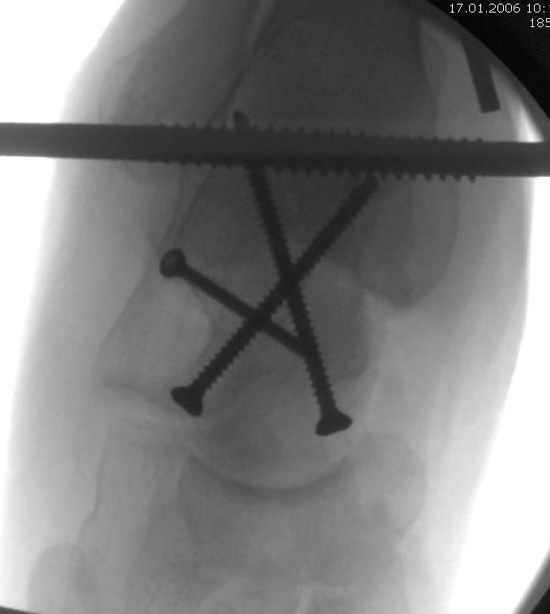

Для доступа к задне-медиальному суставному фрагменту я выполнил косую остеотомию внутренней лодыжки у её основания -получается хороший доступ к голеностопу, адекватный обзор и возможность восстановить суставную поверхность. фрагмент фиксировал двумя 3,5 мм спонгиозными винтами с неполной резьбой, *утопив* головки винтов в кость. Аналогичная фиксация и двумя тягловыми винтами и внутренней лодыжки. \в качестве альтернативы для

фиксации фрагмента тарана можно было бы использовать и герберт винты, но по организационным причинам :-(( набора не оказалось под рукой).

Вывих в таранно-ладьевидном суставе удалось вправить с помощью Howard retractor, используя его в качестве рычага.Сегодня искал в рентген архиве

Вдогонку по поводу перелома таранной кости, больная 81, не страдает диабетом, перелом закрытый, в первый же день поступления ограничились временным наружным фиксатором (как на снимке).

Из-за отека на стопе тактика лечения у всех была

одинаковая: временная наружная фиксация до спадения отека, при изолированных переломах они выписывались домой и через дней 7 госпитализировались на оперативное лечение.

Примеры на снимке...